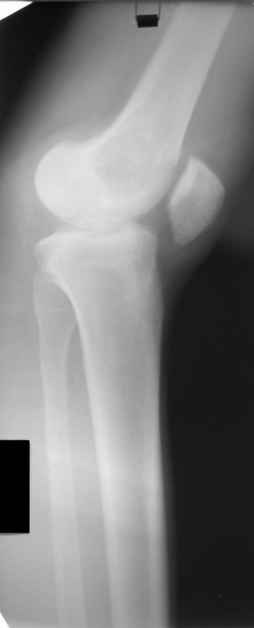

Больной Н., мужчина 18 лет с укорочением бедра и рекурвацией коленного сустава.

Из анамнеза: огнестрельное сквозное пулевое ранение бедра 9 лет назад в н/3 левого бедра. Раны зажили без гнойных осложнений. Жалобы на укорочение левой нижней конечности и нестабильность в коленном суставе. При обследовании выявляется рекурвация коленного сустава. Абсолютное укорочение порядка 5см, стоя 8 см (за счет рекурвации). Имеется умеренный компенсаторный сколиоз. С передне-наружной стороны располагается рубец от входного отверстия, с задне-медиальной стороны от выходного. Можно предположить повреждение при травме зоны роста бедренной кости и задне-внутренних стабилизирующих структур коленного сустава.

A male 18 years old with shortened femur.

Trauma 9 ears ago: gunshot wound with bullet of the left knee. It Is Reeked have healed without festering complications. The patient have shorter femur and recurvatum instability of knee joint. Absolute shortening is 5 cm, at standing up 8 cm (genu recurvatum). The input scar is situated on the antero-lateral side and output scar is on the postero-medial side. It is possible to expect damage by trauma of the growing zone of the femur and back-internal stabilizing structures of the knee joint. We discuss the treatment options: to begin with lengthening of the femur or preferably with stabilizations of the knee joint. What is the optimal level to produce the lengthening of the femur in this case.